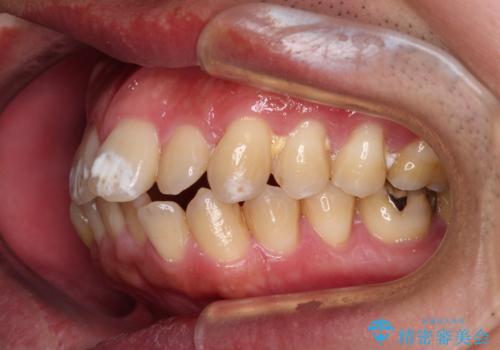

- 口が閉じられないとのことで来院された患者様です。

顎先に力を入れないと唇が閉じきれない口元であったので、上下左右の第一小臼歯4本を抜歯して、ワイヤー装置にて矯正治療を行うこととしました。